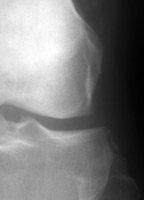

Diagnosis:ACL Tear - Segund fracture Discussion:Frontal radiographs of the knee which reveal a small fleck of bone adjacent to the lateral aspect of the lateral tibial plateau. This "lateral capsular sign" is a simple radiographic finding visible on the routine AP knee x-ray, which indicates severe lateral capsular injury and should alert the examiner to the possibility of ACL tear. The fleck of bone represents an avulsion of the meniscotibial portion of the middle one-third of the lateral capsular ligament. It most commonly implies a disruption of the capsular ligament and the ACL. A-B Radiographs. C. MRI confirms the diagnosis of ACL tear. References: